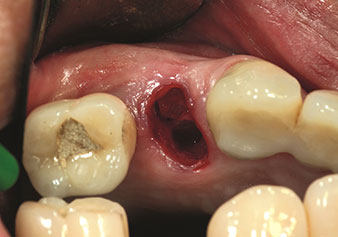

Un’applicazione che viene spesso sottovalutata è l’estrazione atraumatica di radici di denti o frammenti di radici nell’ambito della gestione alveolare. I periotomi sottili, che sono attualmente disponibili in due versioni (EX1 ed EX2 di W&H), possono essere, inoltre, utilizzati per rimuovere con facilità denti che hanno precedentemente subito uno specifico trattamento endodontico o con radici anchilosate. Ne consegue l’estrazione di alveoli in cui i tessuti duro e molle sono entrambi completamente intatti in quanto è generalmente possibile evitare la riflessione.

Ciò pone le basi ottimali per un trattamento con impianto immediato o successivo (Figure 1 e 2 inserite grazie alla gentile concessione del Dott. Torsten Conrad, Bingen a. Rhein).

Situazione in seguito a estrazione con piezochirurgia

Fig. 2: Situazione in seguito a estrazione con piezochirurgia.

Foto: © Dott. Torsten Conrad (Bingen am Rhein)